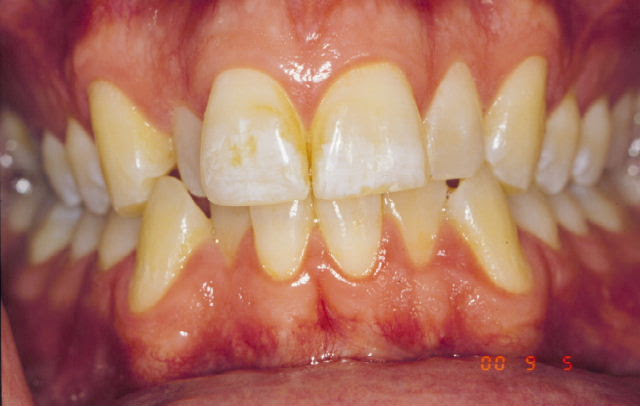

Example of this How to make white spots on your teeth go away